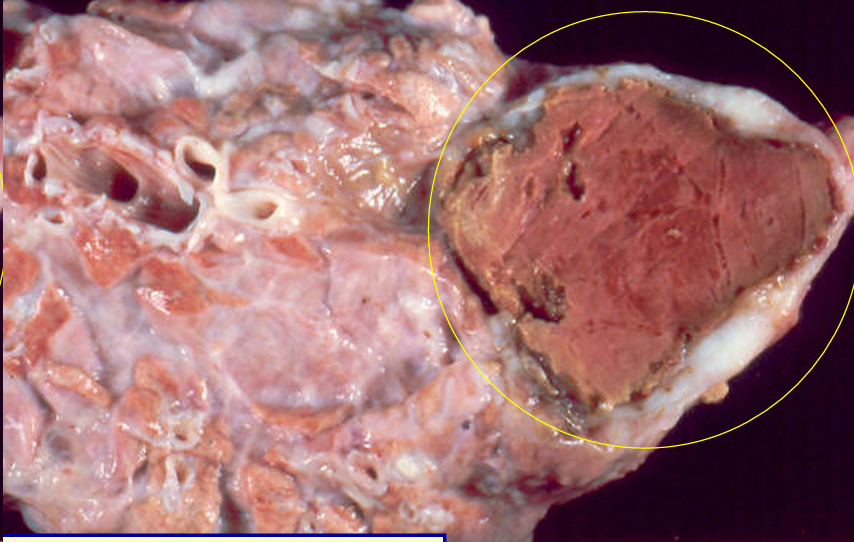

Necrosis caseosa o por caseificación

- Cronica

- Enzimas celulares -> destrucción bacterianas de las celulas normales -> degradación de las membranas liberan lipidos complejos imposibles de digerir

- Etiologia:

- Microorganismos de dificil eliminación como los que producen la tuberculosis, pseudotuberculosis, yersiniosis, aspergilosis

- Tumores de crecimiento rapido

Aspecto macroscopico:

- Color blanco-grisaceo o amarillento

- Consistencia pastosa o grumosa y quebradiza

- Delimitación: Zona de inflamación y capsula conjuntiva

- En linfonodos, higado, riñon

Aspecto microscópico:

- Perdida de la estructura histologica y limites celulares -> restos celulares -> calcificacion

- Masa necrotica delimitada por reaccion inflamatoria

- capsula